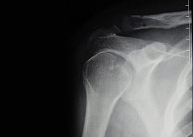

Aunque la región del hombro incluye la clavícula, el omoplato y el extremo proximal del húmero, son las fracturas de este último el grupo más importante por su frecuencia y relevancia. Las fracturas de la porción superior del húmero afectan con mayor frecuencia al paciente de edad avanzada por su menor densidad ósea y en mayor proporción al sexo femenino. En el paciente joven se asocia con traumatismos de alta energía como accidentes de tráfico y deportes de alto riesgo en los que se pueda producir un impacto directo de gran violencia como escalada, motociclismo, ciclismo, esquí, rugby, fútbol americano.El tratamiento dependerá del tipo de fractura y grado de desplazamiento. Las fracturas desplazadas suelen ser subsidiarias de tratamiento quirúrgico. En este caso una cirugía destinada a una movilización precoz con un riesgo mínimo de complicaciones exige un gran conocimiento de la biomecánica articular así como un meticuloso manejo de los tejidos adyacentes al hueso.